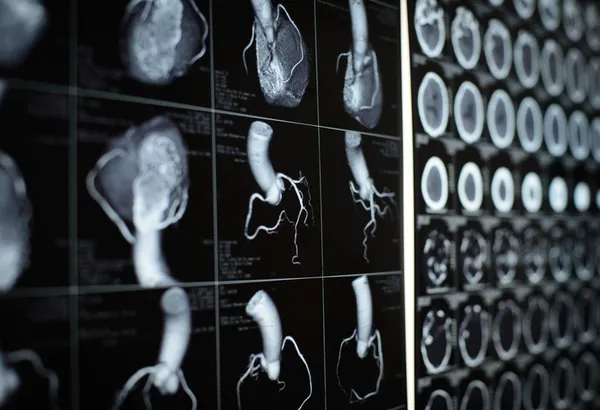

Gül, hastanede düzenlediği basın toplantısında, koroner arter hastalığının tüm dünyada ve Türkiye'deki en önemli ölüm sebeplerinden olduğunu söyledi.

Koroner arter hastalığının, tüm dünyada ve Türkiye'deki en önemli ölüm nedenlerinin başında geldiğini belirten Gül, "Ülkemizde yılda yaklaşık 400 bin civarında bir ölüm olduğunu düşünürsek bunların yüzde 35-40'ı koroner arter hastalığından kaynaklanmakta ve bu çok büyük bir rakamdır. Ülkemizde Trakya bölgesinde ve Edirne ilimizde de koroner arter hastalıkları çok fazla ve pandemiyle birlikte neredeyse bu rakamlar ikiye katlanmış durumdadır." diye konuştu.